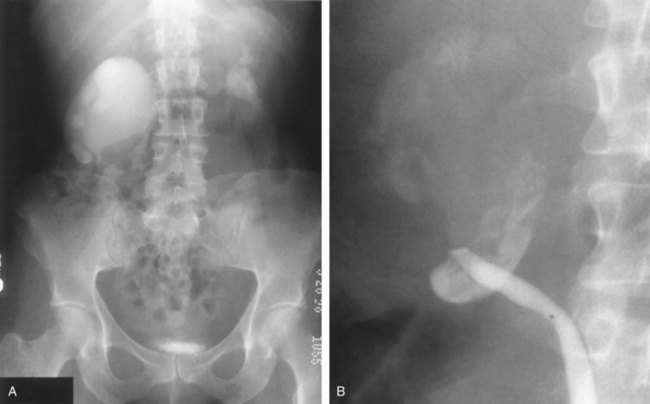

Use of a cautery wire balloon for management of UPJ obstruction was first reported in a clinical series by Chandhoke and colleagues in 1993. Use of this device gained initial acceptance by many clinicians because standard cystoscopic techniques and real-time fluoroscopy are all that is necessary for its use. Because the procedure is guided fluoroscopically, such vessels may increase the risk of hemorrhage after activation of the cautery wire balloon. Some authors recommended preoperative imaging for such vessels with relatively noninvasive techniques such as CT or three-dimensional CT angiography (Fig. 41–12) (Streem and Geisinger, 1995; Quillin et al, 1996; Nakada et al, 1998; Herts et al, 1999; Nakada, 2000). Nadler and colleagues (1996) reported on 28 patients 2 or more years after cautery wire balloon endopyelotomy. With a mean follow-up of 32.5 months, subjective improvement was noted in 61% of patients, and 81% had a patent UPJ on the basis of diuretic renography or Whitaker testing. More recent studies have demonstrated lower success rates than these initial series (32% to 63%) and perhaps that high-grade hydronephrosis has a negative impact on success (Albani et al, 2004; Sofras et al, 2004). El-Nahas and colleagues reported a small prospective randomized trial comparing retrograde ureteroscopic endopyelotomy to the hot-wire balloon endopyelotomy in 40 patients. Although not statistically significant, they found superior success rates (85% compared with 65%) and lower complication rates with the ureteroscopic endopyelotomy (El-Nahas et al, 2006). Ponsky and Streem reported on 64 patients undergoing either ureteroscopic endopyelotomy or hot wire balloon endopyelotomy and found equivalent success rates with both procedures yet higher major complication rates in the cautery wire balloon endopyelotomy, specifically transfusion and selective embolization (Ponsky and Streem, 2006). The major complication associated with cautery wire balloon incision is hemorrhage. Although injury to crossing vessels has been reported using the cutting balloon catheter, strict adherence to lateral incision principles minimizes this risk (Sampaio et al, 1993; Streem and Geisinger, 1995; Wagner et al, 1996). In addition, although some believe crossing vessels hinder success rates primarily, others believe hemorrhage is a real concern (Aslan et al, 1998). Currently, improved ureteroscopic instrumentation and the benefits of direct endoscopic visualization make ureteroscopic endopyelotomy the more pervasive retrograde approach.

Figure 41–12 Spiral CT angiography with three-dimensional reconstruction clearly identifies an accessory lower pole crossing vessels at the level of the ureteropelvic junction (UPJ) in a patient with UPJ obstruction. This case was managed successfully with laparoscopic pyeloplasty.